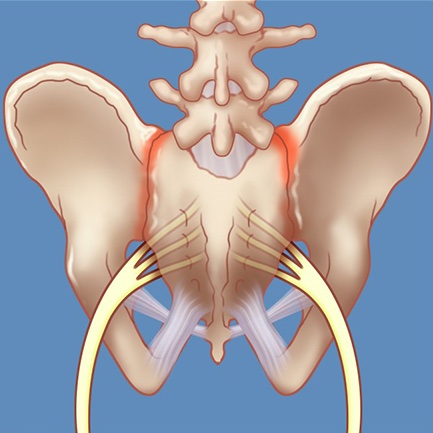

Pelvic Stability

SIJ Dysfunction

Goal: Resolve sacroiliac joint pain

How: Global hip loading and stabilisation to improve joint force closure